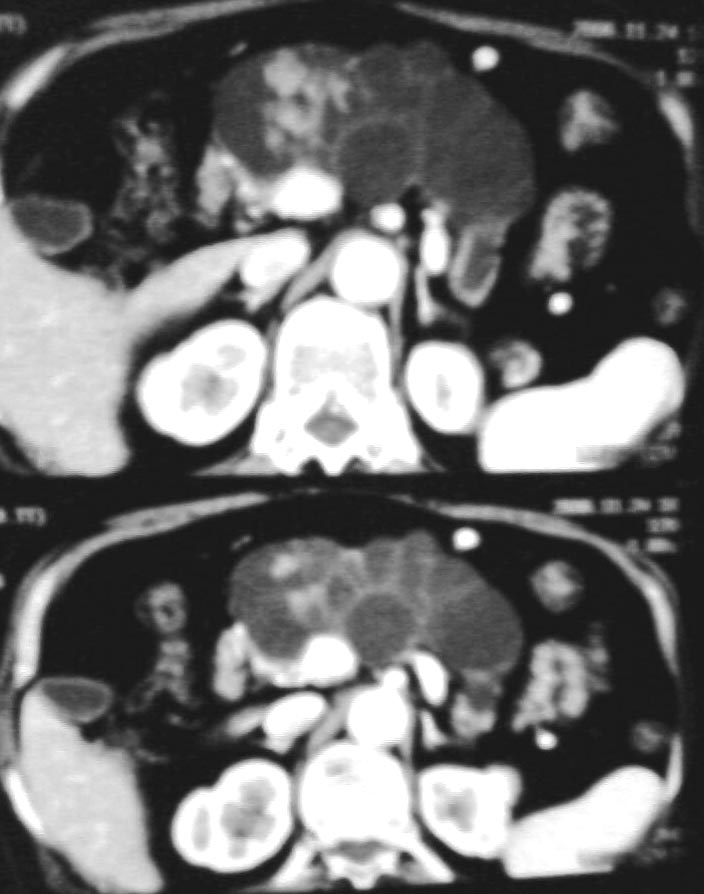

没有见过,能否恳请yzh9939老师转帖其中几幅图片一饱眼福?还有,它与多囊胰腺除了家族史、多伴有多囊肝、多囊肾甚至于脾外还可以怎么鉴别?先谢谢您了!